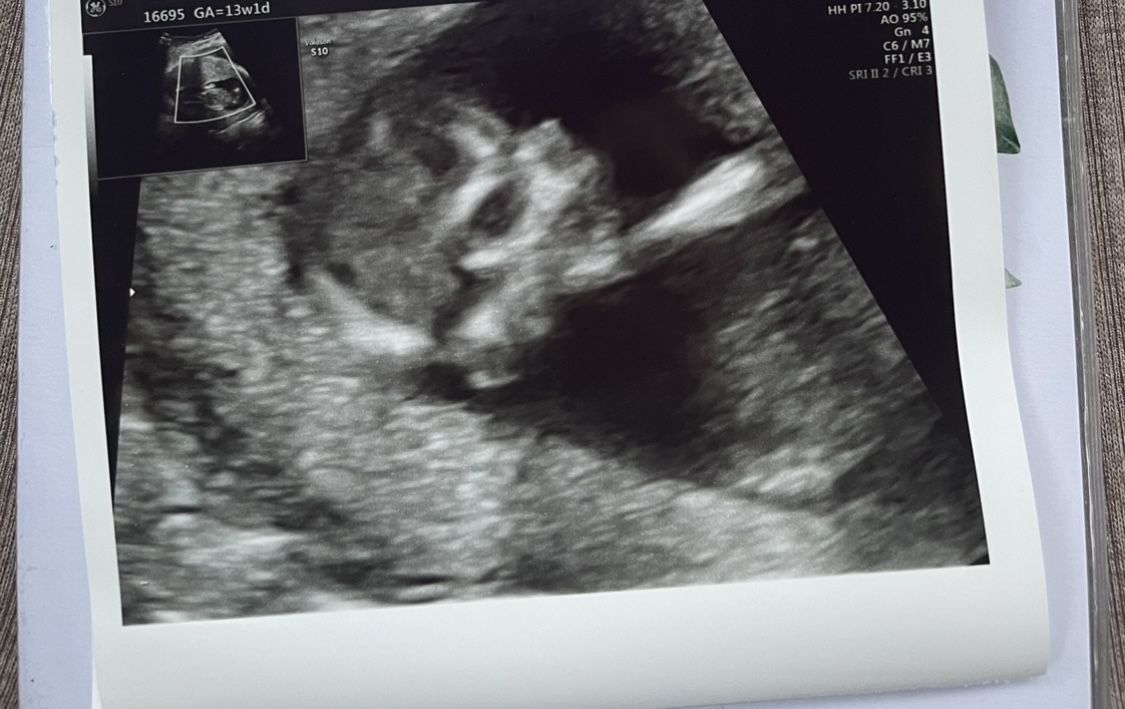

Hallo hier bin ich. Ich kleiner 6,5cm Wurm, habe mich heute sehr bewegt und mir geht es gut. Nächste Woche erfährt Mama, wer ich bin 🙈 bin ich eine kleine Leonie oder doch ein kleiner Jakob ? Was meint ihr ?

mir geht es soweit gut, nackenfalte war auch unauffällig. Die Ergebnisse kommen auch nächste Woche.

Man erkennt ja schon das kleine Köpfchen, das Näs`chen

. ich freuemich so mit dir Nessi

. Ich möchte dir ein Gedicht hier einstellen, was ich für meinen Sohn geschrieben

hatte, als er und seine Frau ihr erstes Kind erwartet haben. Vielleicht freust du dich

darüber.

Herzliche Grüße, Kerstin